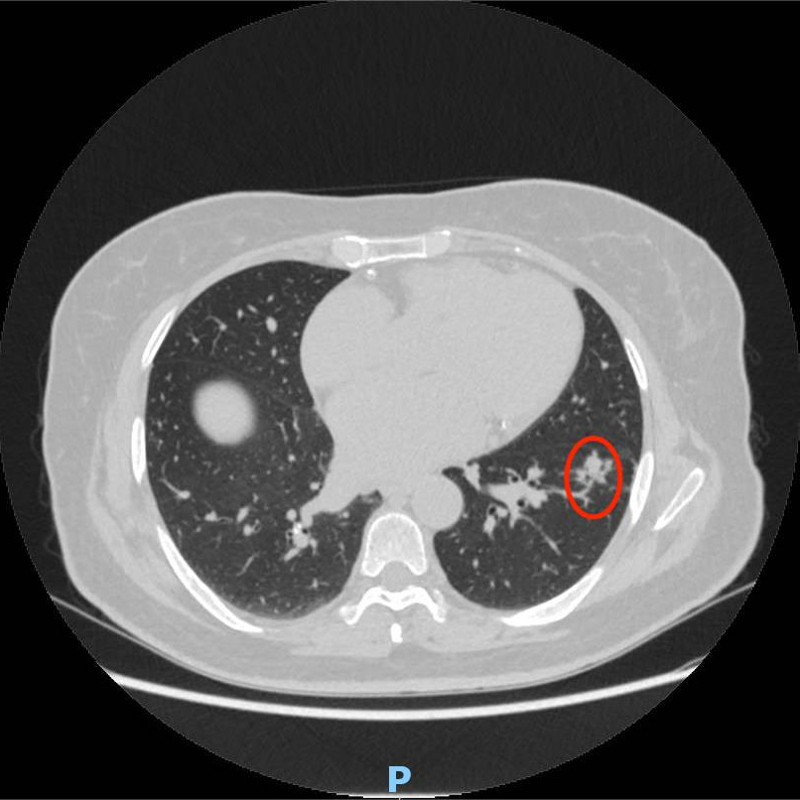

▲术中影像图片

患者手术指征较明确,因其合并有其他基础病,于是在围术期前期给予降压、控制血糖、抗凝等治疗。综合考虑患者病灶部位、手术耐受性、合并多种基础病等原因,在经过多学科联合会诊讨论后为患者制定了个性化的手术治疗方案,最后由唐中明主任与主管医师危云辉在CT引导下行经皮左下肺结节微波消融术+左下肺结节穿刺活检术,术后病理提示为肺腺癌。